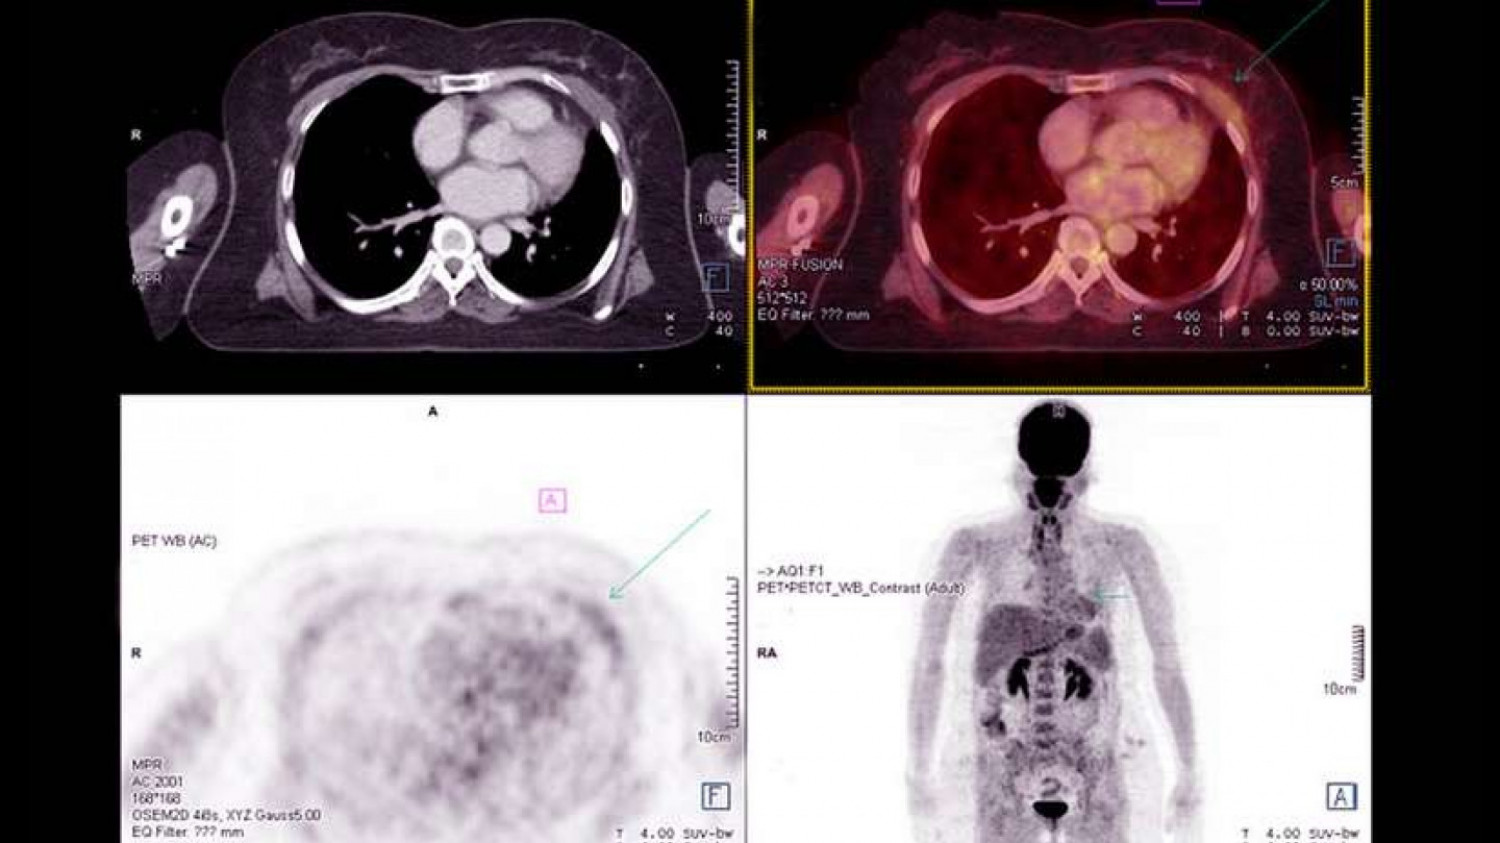

Positron Emission Tomography/Computed Tomography (PET/CT) provides the combined benefit of PET, which detects changes in cellular structure at the molecular level, and CT, which provides three dimensional images of bone and soft tissue. Your physician receives precise results for diagnosis and treatment planning.

PET/CT is used in diagnosis and treatment planning for cancer. It is used to detect cancer, determine whether cancer has spread in the body, assess treatment, determine reoccurrence, or to confirm cancer free after treatment.